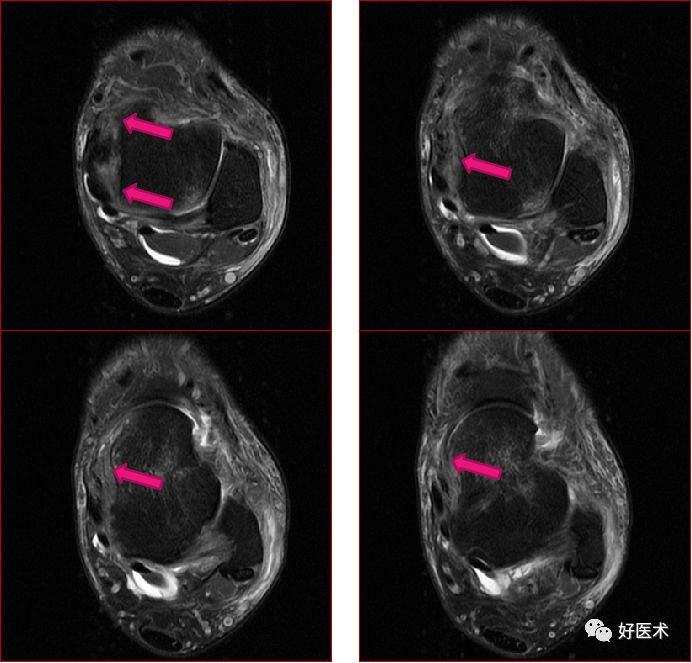

三、骨软骨病变

距骨骨软骨损伤,好发于前外侧、后内侧,尤其是后内侧,与内外翻损伤相关。

距骨骨软骨损伤分级

1度损伤:

2度损伤

3度损伤